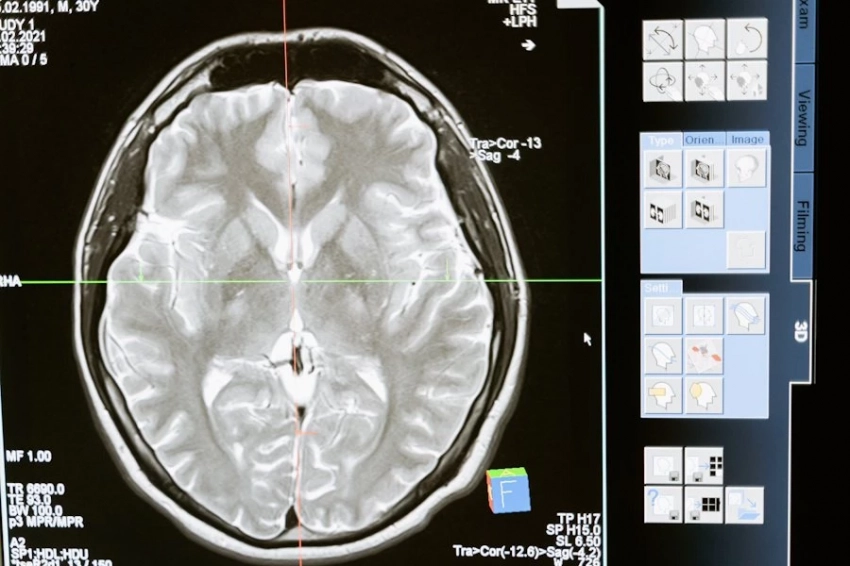

Уникальный случай зафиксировали ученые: мозг 87-летнего пациента продолжал работать 15 минут после остановки сердца.

Электроэнцефалограмма показала активность в областях, отвечающих за память

Ученые предполагают, что мозг воспроизводил последние воспоминания.